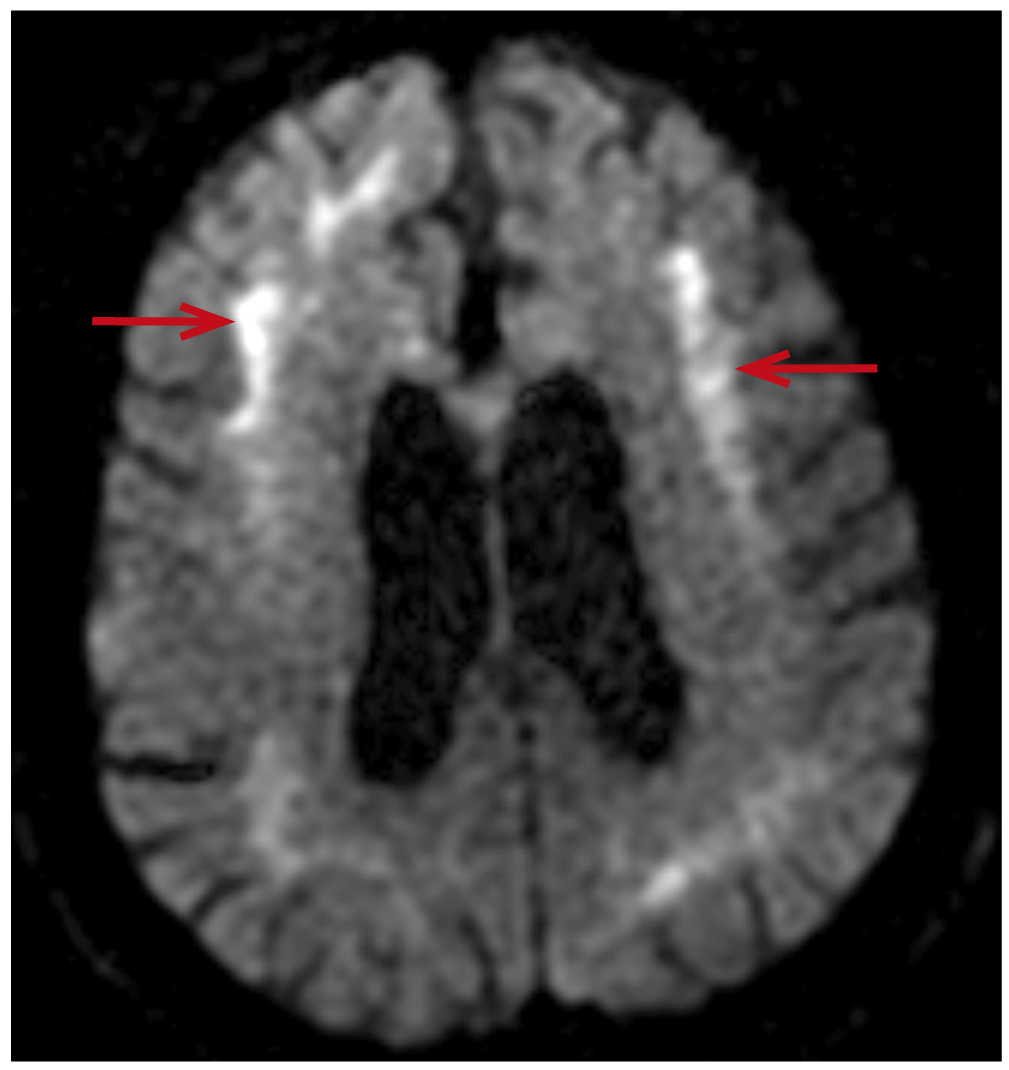

On 01.11.2024, in the morning he could not get up from his bed, had an episode of dizziness with developing weakness in the whole body, especially in the lower limbs, after which he fell. At the In-Patient Department, Brain MRI was conducted using the diffusion-weighted mode (Diffusion Weight Imaging, DWI): symmetrical signal increase from the corticomedullary junction of the brain hemispheres, from the fibers of the corpus callosum and from the substance of the middle peduncles of the cerebellum (Fig. 1).

Fig. 1. Symmetrical DWI-hyperintensity at the level of the corticomedullary junction on both sides at the frontal (arrows) and parietal lobes.